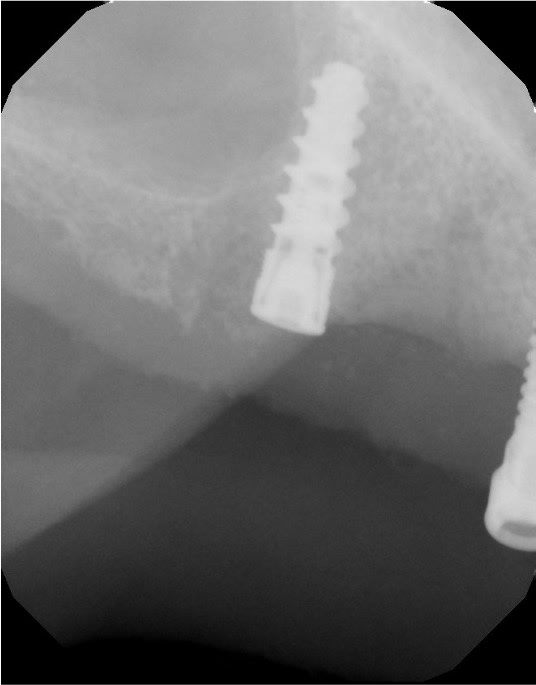

A 67-year-old female patient had a chief complaint of being unhappy with a previously fabricated full palate covered LOCATOR overdenture. The implant positioning was adequate, but the AP spread was not suitable to retain a palateless overdenture nor a fixed implant prosthesis. Five implants had apparently been placed previously but the maxillary right implant had not integrated properly and was removed prior to her evaluation in this practice. There were no significant health issues or medication concerns. She requested “permanent teeth” to improve her quality of life, function, and esthetics. The periodontal health around the existing dental implants was good, with no significant concerns. Figure 1 illustrates the esthetics created by the recently made maxillary and mandibular LOCATOR overdentures. The dentures provided some increased stability and function, but the patient’s concern was that they were not what was promised (Figure 2). CBCT analysis indicated some compromised bone contours where the maxillary right posterior implant has been avulsed (Figure 3). A newly placed fifth dental implant was needed to support any fixed prosthesis in this compromised edentulous arch. A new 3.5 mm x 10 mm HT™ dental implant (Glidewell, glidewelldental.com) was strategically positioned in front of the large maxillary sinus to provide distal support for the final prosthesis (Figure 4).

The 3.5 mm x 10 mm HT dental implant successfully integrated in the available hard tissue in the maxillary right second bicuspid area. The implant had been allowed to integrate for approximately 4 months and the patient wore the existing fabricated full palatally covered implant-retained LOCATOR overdenture during the healing period.